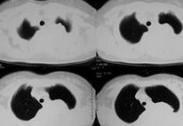

腫瘤性胸腔積液亦稱惡性胸腔積液。大多數病例可以在胸腔積液中找到惡性細胞,如果胸腔積液伴縱隔或胸膜表面轉移性結節,無論在胸腔積液中能否找到惡性細胞,均可以診斷惡性胸腔積液。